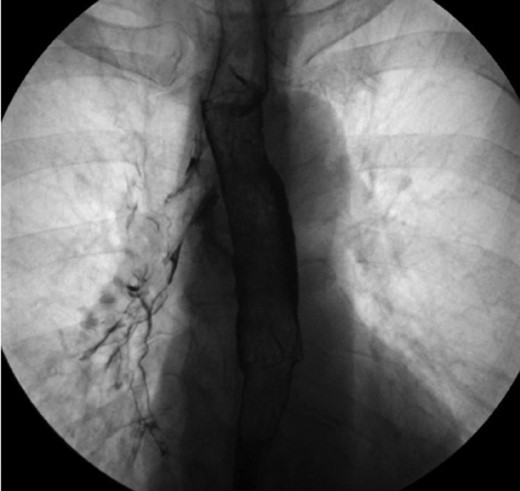

The patient was a 66-year-old white female with history of Histoplasmosis capsulatum infection and diabetes who presented as an outpatient with hemoptysis for 6 weeks. The patient was a lifelong non-smoker. A computer tomography (CT) scan of the chest revealed a calcified subcarinal lymph node along with an obstructing endobronchial lesion on the medial wall of the right mainstem bronchus (Fig. 1A). A rigid bronchoscopy was performed revealing an endobronchial mass causing a 50% obstruction of the right mainstem bronchus (Fig. 1B). The cryotherapy probe was used for mass excision and a full mediastinal staging was performed using endobronchial ultrasound (EBUS) bronchoscopy. The right mainstem bronchus was recanalized with return to 100% patency. Histology from the mass revealed an inflammatory polyp. The etiology of the inflammatory polyp was presumed to arise from inflammation stemming from the calcified station 7 lymph node abutting the medial wall of the right mainstem bronchus.

(A) Calcified subcarinal lymph node. (B) Obstructing endobronchial lesion on the medial wall of the right mainstem bronchus.